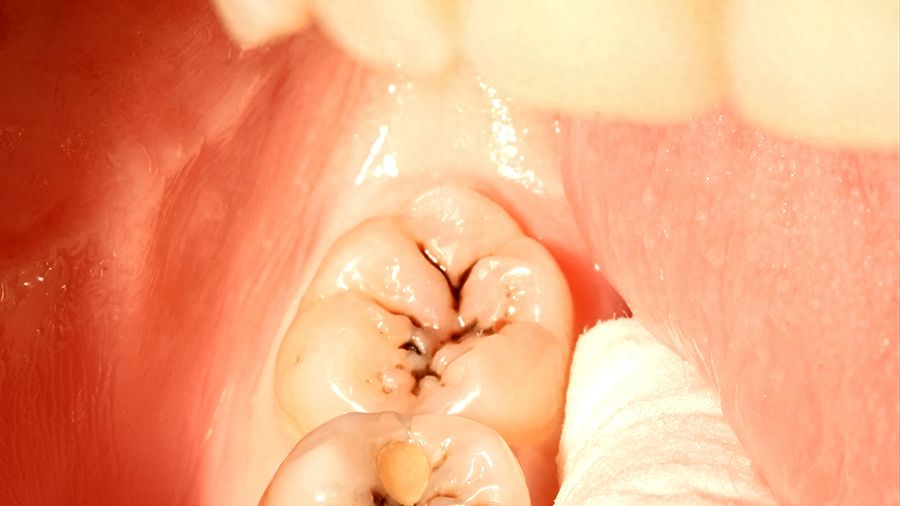

洗牙、拔智齒、補牙:常見項目價格親民

相比于其他項目,洗牙、拔智齒、補牙等常見項目的價格相對親民。在無錫口腔醫(yī)院,超聲波洗牙從108元起,拔牙從198元起,為患者提供了貼心的服務。